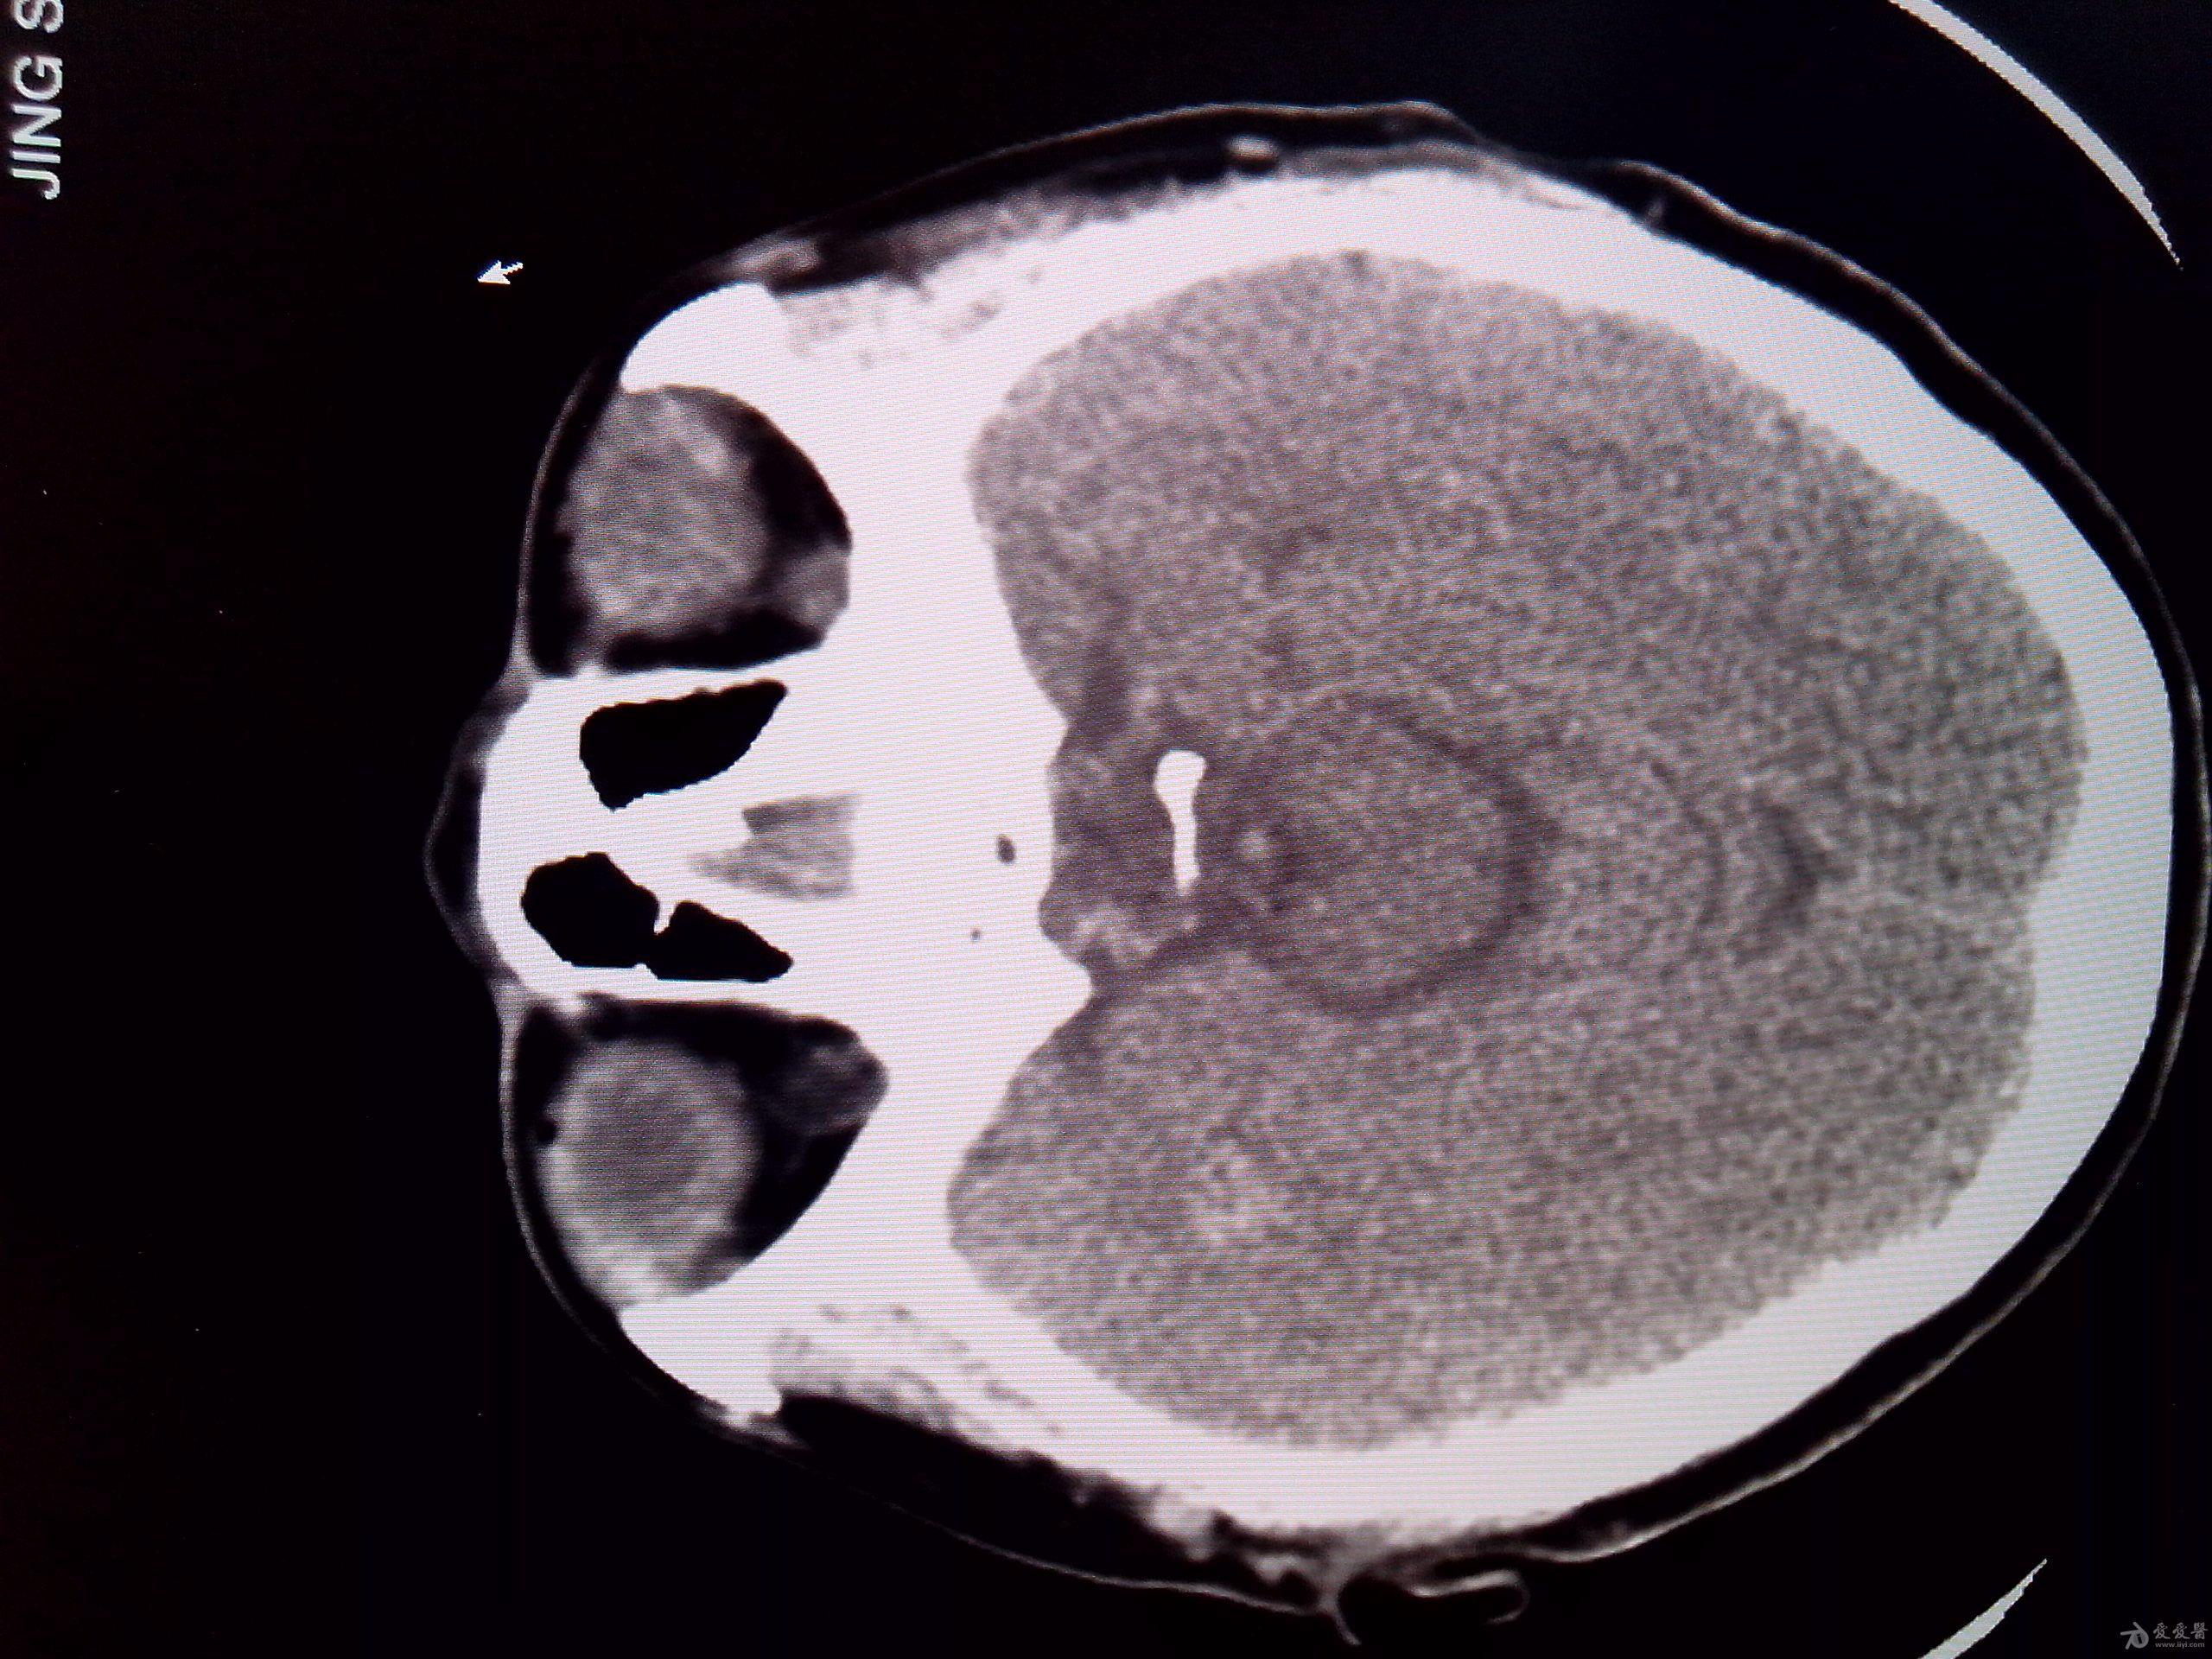

mri影像显示,患者左侧额颞叶部较大面积血肿

图片尺寸500x503